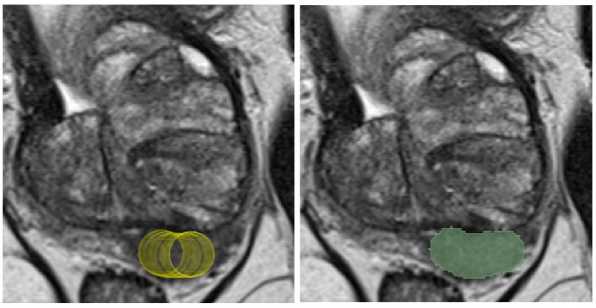

Вторым этапом осуществлялась тестовая разметка двумя врачами-рентгенологами с опытом работы в урогенитальной лучевой диагностике 3 и 4 года (разметчик 1 и разметчик 2). Для разметки применялось расширение mpReview в программном обеспечении 3D Slicer. Врачи-рентгенологи независимо друг от друга, а также без предварительного ознакомления с консенсусной разметкой, выполнили оконтуривание очагов, соответствующих критериям PI-RADS 3, 4, 5, используя контурную кисть (инструмент Draw) (Рис. 1) и обычную кисть (инструмент Paint) в виде круга (region of interest – ROI) и сферы (volume of interest – VOI). Используя инструмент Paint в виде круга (ROI), рентгенолог закрашивал зону интереса на одном срезе или нескольких срезах поочередно (Рис. 2). При применении инструмента Paint в виде сферы (VOI) (Рис. 3) разметчик выбирал необходимый диаметр и выделял область интереса (Рис. 3), то есть часть очага с визуально наиболее выраженными изменениями. Если очаг имел неправильную или овоидную форму, диаметр сферы выбирался исходя из наибольшего поперечного размера очага во избежание включения окружающих неизмененных тканей в маску. В тех случаях, когда диаметр сферы был равен толщине среза, в связи с техническими ограничениями VOI заменялся ROI. На примере используемого в нашем исследовании набора данных с указанной толщиной среза (Табл. 1) пограничным диаметром сферы являлся 8 миллиметров. При наличии нескольких патологических очагов в одном исследовании сегментация очагов производилась в соответствии с референсными изображениями и осуществлялась поочередно, начиная с правой доли простаты и продвигаясь сверху вниз. Такой порядок сегментации способствовал исключению несоответствий в масках конкретного очага между двумя экспертами в случаях мультицентрических форм. Результирующая маска и серии изображений (Т2-ВИ, ДВИ, ИКД) сохранялись в формате NIfTI (.nii). Время оконтуривания очага каждым методом разметки измерялось при помощи макроса Microsoft Excel оригинальной разработки. При нажатии кнопок «Старт» и «Финиш» фиксировалось текущее время рабочей станции; время разметки вычислялось как арифметическая разница между двумя нажатиями.

Рис. 1. Контурная кисть. Для создания маски очага разметчик выбирал инструмент Draw и поочередно оконтуривал очаг на всех срезах.

Рис. 2. Обычная кисть в виде круга (ROI). Для создания маски очага разметчик выбирал инструмент Paint в виде круга (ROI) и поочередно выделял очаг на всех срезах.